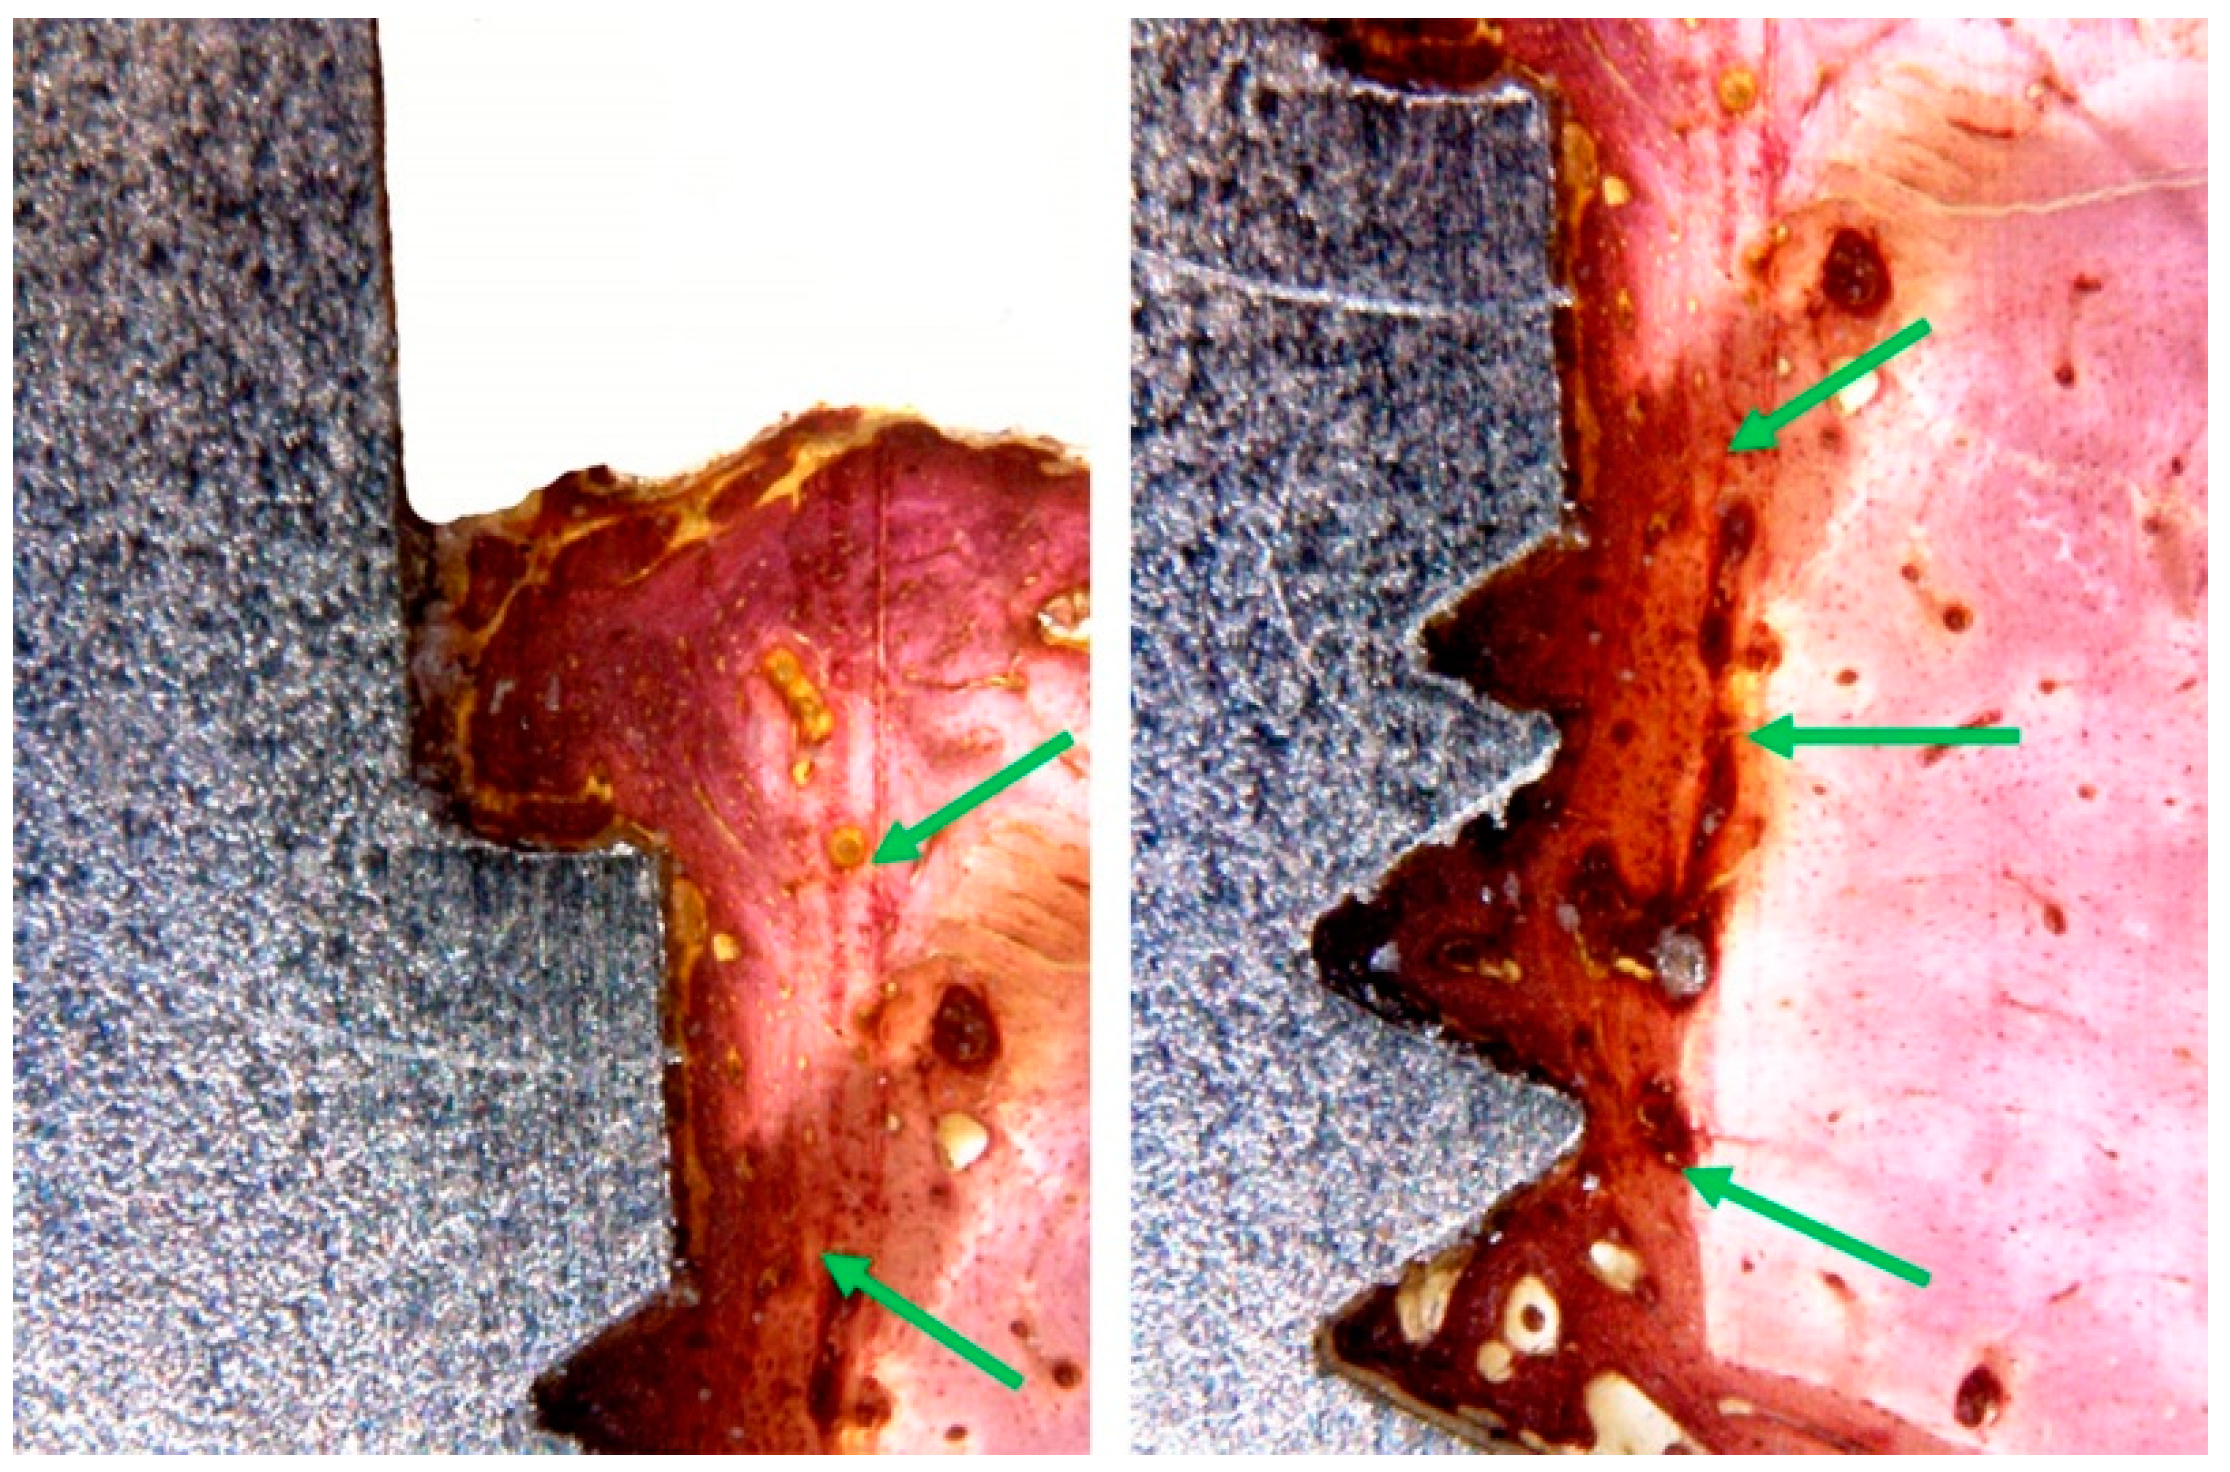

3.3. Histomorphological Analysis